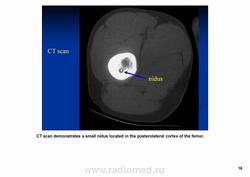

Остеоидная остема.

Диагностика и дифференциальная диагностика.